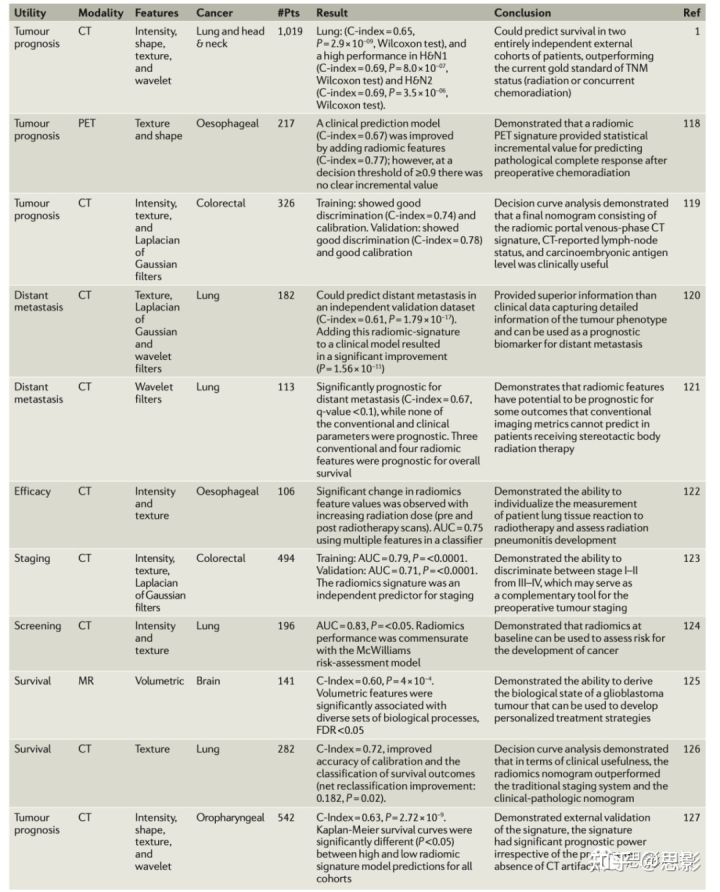

自本世纪初以来,影像组学研究取得了显著进展,揭示了这一学科在大幅改善临床护理方面的潜力(表2)。硬件和软件的进步使组织病理生理学的临床可行性定量成像得以实现。

表2 影像组学实践